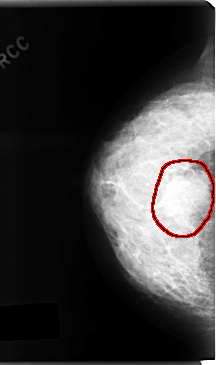

C_0166_1.RIGHT_CC

RIGHT_CC LINES 4736 PIXELS_PER_LINE 2808 BITS_PER_PIXEL 12 RESOLUTION 50 OVERLAY

FILE: C_0166_1.RIGHT_CC.OVERLAY

TOTAL_ABNORMALITIES 1

ABNORMALITY 1

LESION_TYPE MASS SHAPE OVAL MARGINS SPICULATED

ASSESSMENT 5

SUBTLETY 5

PATHOLOGY MALIGNANT

TOTAL_OUTLINES 1

BOUNDARY